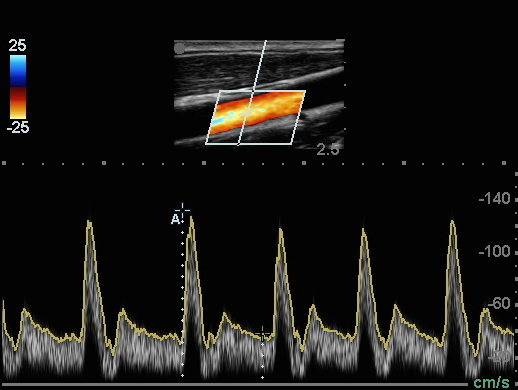

颈动脉颈总动脉 (CCA) 多普勒测量图像